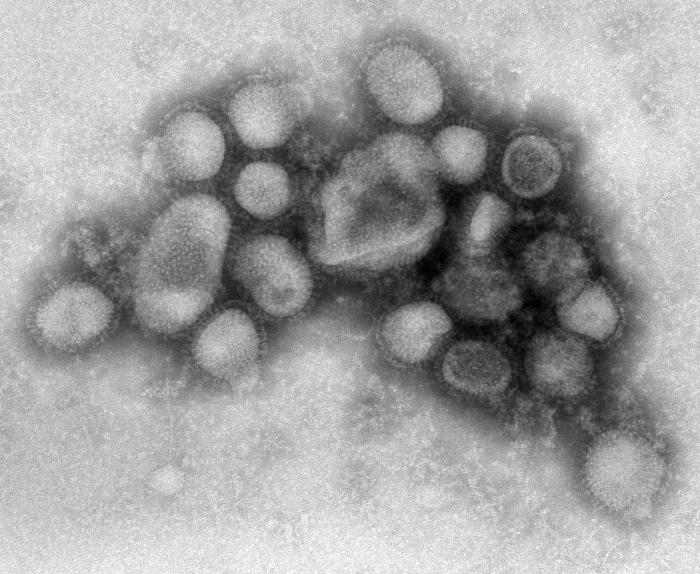

Influenza

The flu needs little introduction. It circulates every fall and winter, and severity ranges from a few miserable days to hospitalization and death. For children, the risks include pneumonia, dehydration, and worsening of underlying conditions like asthma. Healthy children die from the flu every year. In the 2024-2025 flu season, 288 children in the United States died from influenza. The highest toll of any regular season since the CDC began tracking pediatric flu deaths in 2004. 89% of them were unvaccinated. These numbers are not unusual. Pediatric flu deaths occur every season, and the majority consistently occur in children who did not receive the vaccine.

The flu vaccine differs from most other childhood immunizations because it requires an annual shot. The virus mutates constantly, and each year’s vaccine is reformulated to match the strains expected to circulate. This makes it less convenient and, for some, less urgent than vaccines that provide long-lasting protection from a single series. But the annual death toll among children suggests otherwise.

Health officials recommended flu vaccination for all children. Not only because children get sick, but because they spread the virus efficiently to grandparents, immunocompromised family members, and others who face far higher risks from infection. Removing the universal recommendation shifts that calculus to individual families.